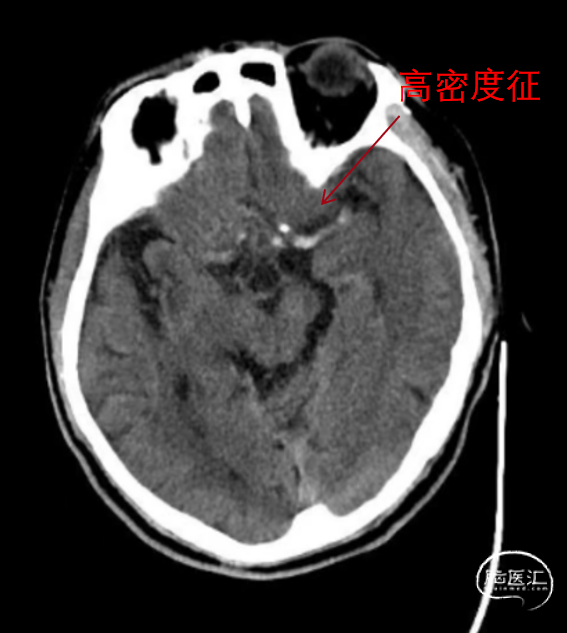

查血常规、生化、凝血未见异常;心电图提示心房纤颤;头颅CT示多发性脑梗死,左侧大脑中动脉高密度征;头颅CTA提示左侧颈内动脉末端闭塞。拒绝静脉溶栓治疗,转至我院行急诊机械取栓。

头颅CT